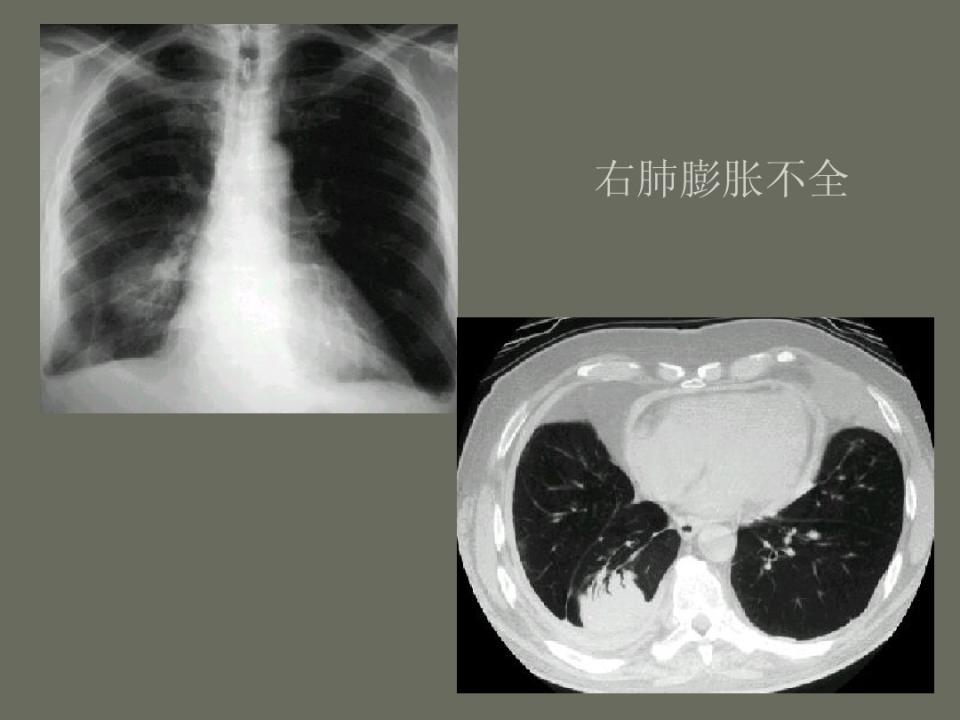

肺部先天性疾病的影像诊断